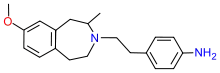

4-Phenylpiperidines

Pethidines (meperidines)

- 4-Fluoropethidine

- Allylnorpethidine

- Anileridine

- Benzethidine

- Carperidine

- Difenoxin

- Diphenoxylate

- Etoxeridine (carbetidine)

- Furethidine

- Hydroxypethidine (bemidone)

- Morpheridine

- Meperidine-N-oxide

- Oxpheneridine (carbamethidine)

- Pethidine (meperidine)

- Pethidine intermediate A

- Pethidine intermediate B (norpethidine)

- Pethidine intermediate C (pethidinic acid)

- Pheneridine

- Phenoperidine

- Piminodine

- Properidine (ipropethidine)

- Sameridine

Structures